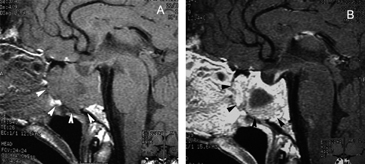

A diferencia de la tomografia computada, que emplea tubos de rayos X, la RM no utiliza radiaciones ionizantes, lo que es una ventaja a considerar en los pacientes pediátricos y en las mujeres embarazadas. La RM tiene una excelente resolución espacial y de tejidos blandos; por ejemplo permite precisar la presencia o ausencia de la neurohipófisis, lo que no es posible con la Tomografia Computada5-7. Con la TAC, con o sin medio de contraste yodado, es posible detectar microadenomas y macroadenomas pituitarios (Figuras 1A y 1B); sin embargo, en los macroadenomas puede ser difícil distinguir las relaciones del tumor con el quiasma óptico, o definir la invasión del seno cavernoso. Además, los artefactos producidos por amalgamas dentales deterioran las imágenes y la dificultad para lograr posiciones cómodas para los pacientes, con el fin de obtener cortes coronales directos, limitan la utilidad de la TAC.

Figura 1A y B. TAC con contraste yodado, corte coronal, muestra un microadenoma lateralizado a izquierda (punta de flecha). Control a los 2 años. TAC con contraste yodado, corte coronal, demuestra aumento de volumen del microadenoma, lo que es infrecuente de observar en clínica (punta de flecha).